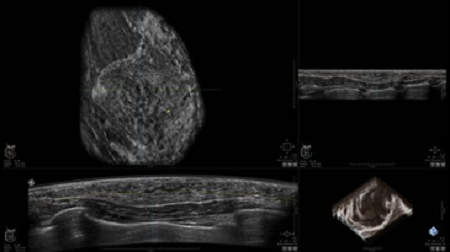

УЗИ-аппарат

GE INVENIA ABUS 2.0

GE INVENIA ABUS – это современный УЗИ аппарат, который создан для точной и эффективной диагностики сканирования с высокой плотностью молочных желез. Выявляемость патологий раковых и предраковых стадий заболевания составляет 55%, что в конечном счете позволяет ставить врачу точные и своевременные диагнозы. Традиционные методы использования маммографии не показывают такой выявляемости, ограничиваясь лишь 3-38%.

УЗИ-аппарат GE INVENIA ABUS позволяет проводить максимально операторонезависимые процедуры, что значительно снижает риск неправильной постановки диагноза и сопутствующие издержки на обработку информации. Система готовит отчет в течение 3-х минут после сканирования, это безусловное преимущество по сравнению с обычным УЗИ сканером.

• датчик с изогнутой апертурой для качественного исследования

• сканирование одной грудной железы в трех проекциях не более 60 сек.;

• обработка результатов за три минуты.

Данное устройство классифицируется, как стационарное, используемое в многопрофильных клиниках, женских консультациях, медицинских центрах. Вес без учета дополнительного оборудования составляет 105 кг. Удобная колесная база позволяет оперативно маневрировать в ограниченных пространствах, в том числе передвигать устройство в коридорах клиники. Большой 17-ти дюймовый монитор с широкими углами обзора выводит максимально качественную картинку в формате Full HD.

• Получение объемных 3D изображений с возможностью покадрового просмотра

• Получение изображений в поперечной плоскости (в реальном времени) и в коронарной плоскости (статическая, для указания нахождения соска)

• Отображение объемных 3D ультразвуковых изображений, которые состоят из традиционных поперечных и воссозданных коронарных и сагиттальных проекций

• Возможность отображения полного 3D изображения

• Стандартизованная ориентация изображения: «толстый срез» в коронарной плоскости; поперечная; сагиттальная плоскость; радиальный и антирадиальный поворот изображения; просмотр исключительно области интереса